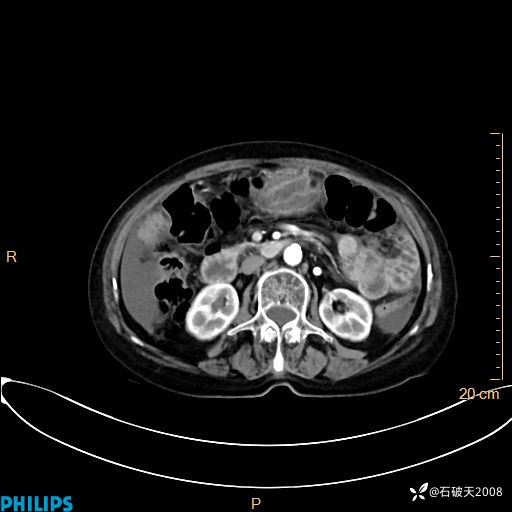

静脉期